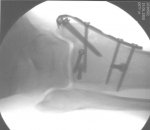

habe mir leider in Hechlingen eine Fraktur des Sprunggelenks und einen 2 fachen Syndesmoseabriss zugezogen und habe seit Freitag eine kleine Titanschraube im Gelenk. Ist schon blöd wenn das Moped eine andere Vorstellung von der Marschrichtung hat als der Fahrer.